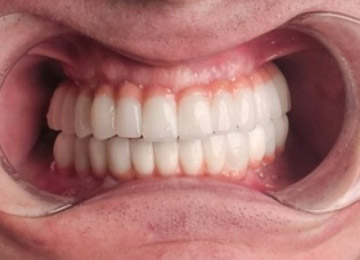

Имплантация зубов: фото «До» и «После»

All-on-4

All-on-6